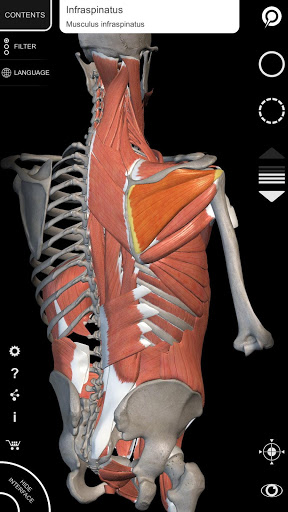

"Anatomy 3D Atlas" vous permet d'étudier l'anatomie humaine de manière simple et interactive.

Grâce à une interface simple et intuitive, il est possible d'observer chaque structure anatomique sous n'importe quel angle.

Les modèles anatomiques 3D sont particulièrement détaillés et avec des textures jusqu'à une résolution de 4k.

• Système musculo-squelettique

• Visualisation des muscles à travers des niveaux de couches depuis les plus superficielles jusqu'aux plus profondes

• Description des muscles : origine, insertion, innervation et action